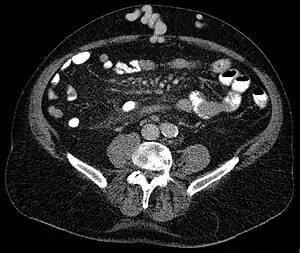

Axial CT showing portosystemic collateral circulation via the umbilical vein: caput medusae in liver cirrhosis